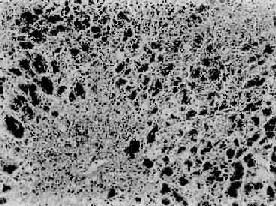

本病发病机制尚未完全阐明,以前认为FHF的发病主要是原发性免疫损伤,并继发肝微循环障碍。但随着细胞因子(Cytokine)对血管内皮细胞作用研究的深入和对肝微循环障碍在发病中作用的研究,认为Schwartz反应与FHF发病有关。

细胞因子是一组具有生物活性的蛋白质介质,是继淋巴因子研究而生出来的,如肿瘤坏死因子(TNF),白细胞介素-1(IL-1)及淋巴毒素(LT)等,其中TNF是内毒素刺激单核巨噬细胞的产物,并能作用于血管内皮细胞及肝细胞,可导至Schwartz反应,因而认为TNF是FHF的主要发病机制之一,此外,内毒素血症可加重肝细胞坏死和导致内脏损伤(如肾功能衰竭)也是一个重要致病因素。